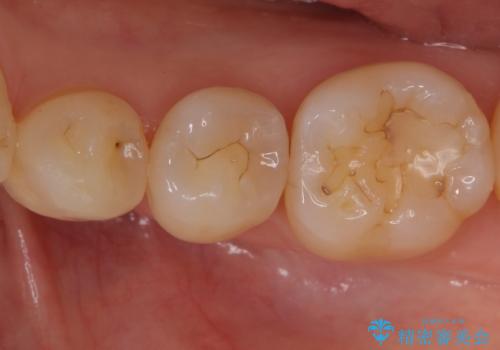

- 奥歯の樹脂の色が気になるとのことで来院されました。

変色しない材料での治療をご希望されたためセラミックインレーでの治療をしていくこととなりました。

継ぎ接ぎになった樹脂の詰め物から一塊のセラミックインレーに置き換えることで着色や二次う蝕のリスクを抑えます。